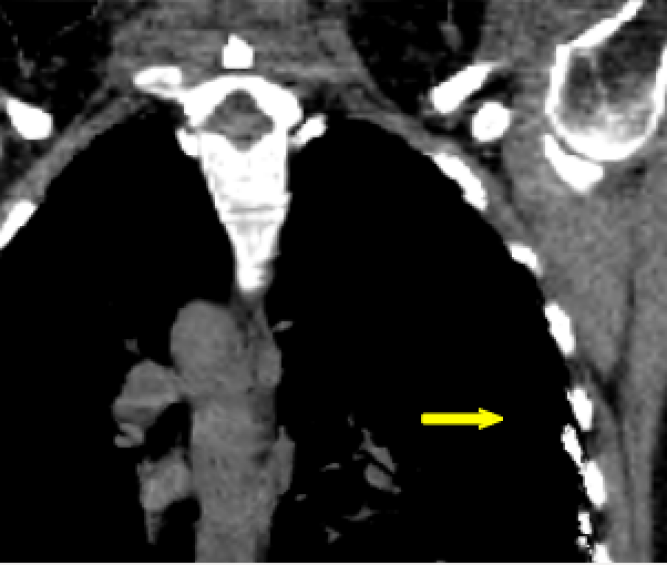

The mean DICE coefficients of the single-atlas registration of the liver and lung masks to the new static patient yield satisfying values of 0.860.12 and 0.960.09. Note the clearly different scan ranges of the data sets (Fig. 2a). The animation of the relevant structures is shown as an example in Fig. 3, using a variable real breathing signal of the target patient (Fig. 2b). In the puncture-relevant liver region, the patient’s breathing states are simulated plausibly for the 4D reference patient (Fig. 3) and, more importantly, the 3D patient (Figs. 4, 5), to which the motion model of was transferred333Demo movie, click here.

We achieve qualitatively plausible results for the liver area in this feasibility study. In the upper thorax especially at the rib cage in neighborhood to the dark lungs stronger artifacts can occur (Fig. 5c). They are due to problems in the inter-patient registration that is a necessary step for the transfer of the motion model. The non-linear deformation sometimes is prone to misaligned ribs. The same is true for the lower thorax with perforation first of the liver and then diaphragm (Fig. 4c). Further optimization have to be carried out as artifacts can appear on the high contrast lung edge (diaphragm, ribs) with a small tidal volume. For liver punctures only, the artifacts of smeared ribs are minor as can be seen in Fig. 4.